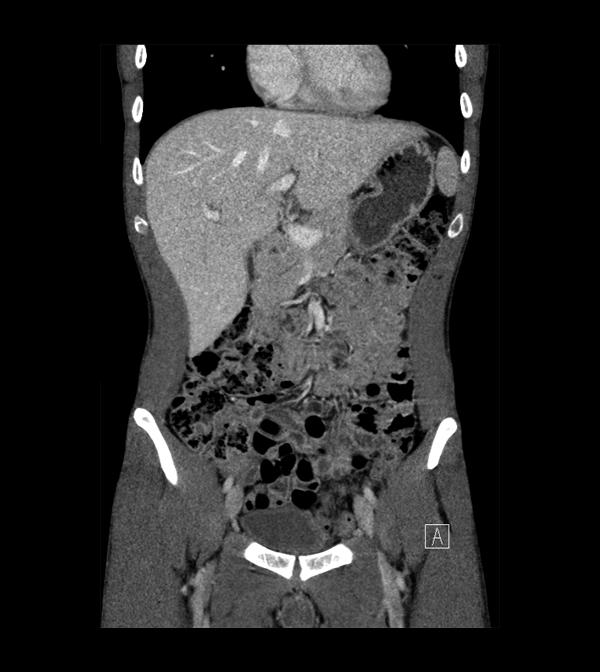

Body

Covers abdominal CT anatomy.